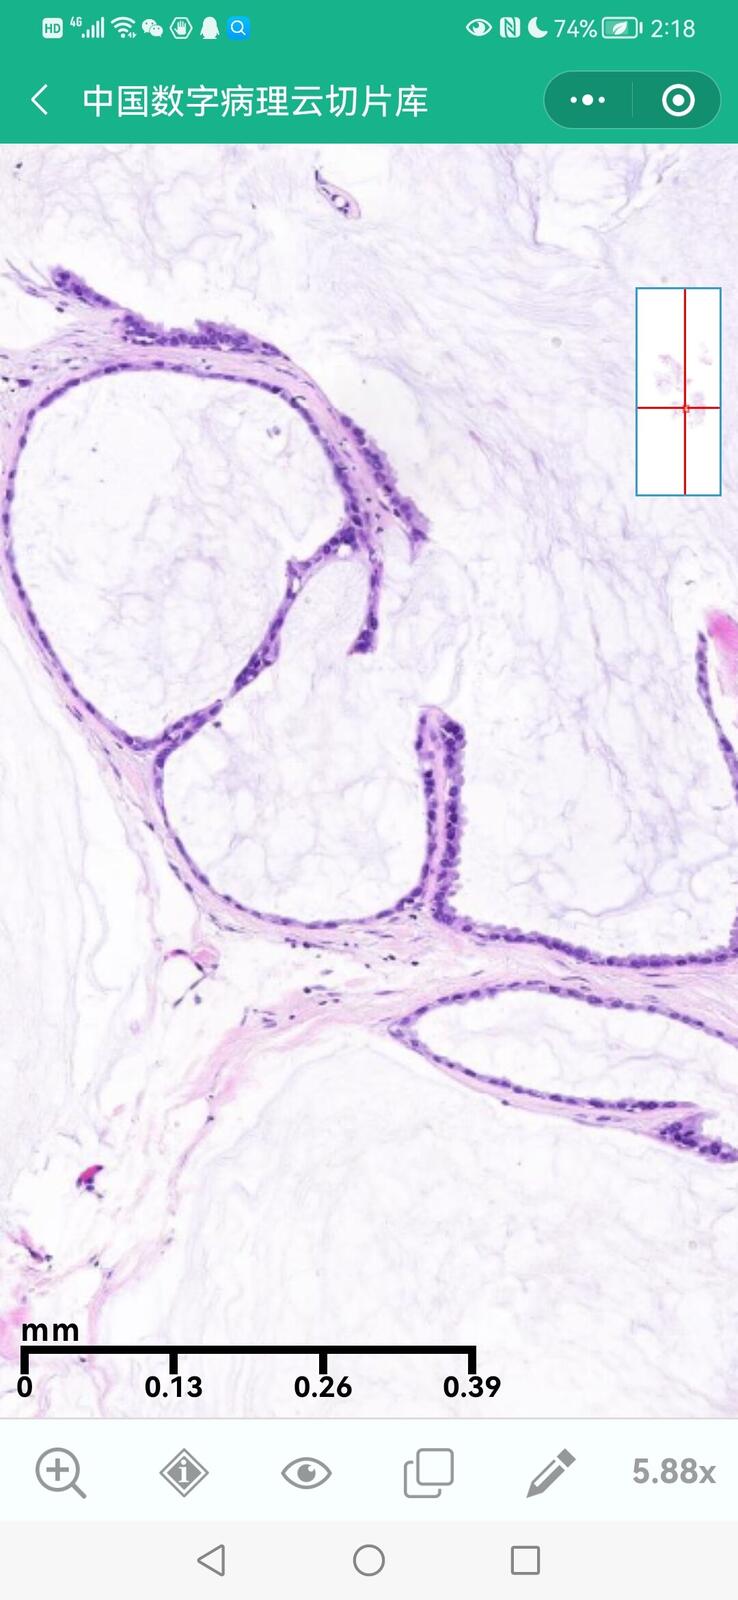

乳腺黏液性囊腺瘤伴导管内癌